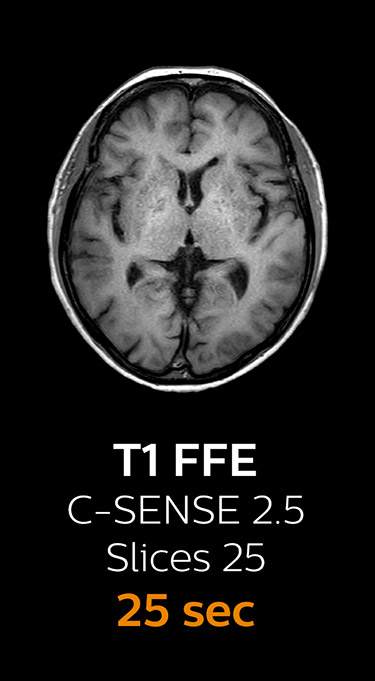

“We now only need about 10 minutes of scan time for a brain exam – and we still get the same amount of images and equal quality. We even managed to make a very useful improvement: we replaced the 43-second T21 FFE by a 43-second SWIp, which is more powerful for us in making confident diagnoses in certain patients.” “SWIp was not previously included in our standard protocol, because of its slightly longer scan time. SWIp provides high resolution 3D susceptibility weighted imaging in the brain, which helps to visualize small deoxygenated blood or calcium deposits. Now, with Compressed SENSE, we can perform 3D SWIp in only 43 seconds, so we have included SWIp instead of the 2D T21 FFE that we used previously. Without adding scan time, we now get SWIp images in every routine brain scan and it helps us increase our diagnostic confidence in certain cases.”

Scanning time reduction in brain MRI with Compressed SENSE

Fast MRI of brain

With Compressed SENSE, the scan time for the routine brain examination at KNC was reduced from 15:48 to 10:19 minutes, which corresponds to 35% reduction.

Ingenia 3.0T CX

Scan time 15:48 min.

Brain with Compressed SENSE

Ingenia 3.0T CX

Scan time 10:19 min.